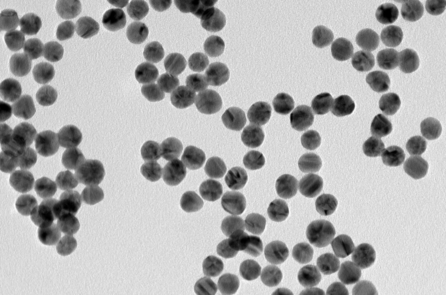

Mặc dù có những đặc tính hữu ích nhưng catechin ít được dùng làm tác nhân trị liệu vì khả năng hấp thụ kém, sinh khả dụng thấp và thoái hóa nhanh chóng. Tuy nhiên, các nhà khoa học đang áp dụng công nghệ sinh học nano để giải quyết những vấn đề này.